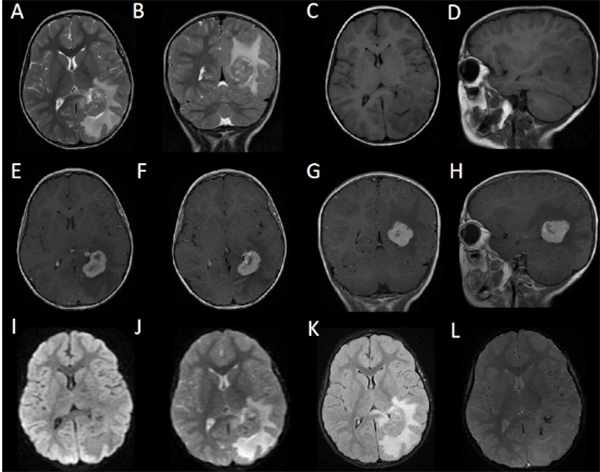

El informe histopatológico fue compatible con Schwannoma (Figura 2).

Figura 2: Cortes histológicos de la pieza. Se observan células bipolares ausadas con bajo índice de mitosis. Alternan areas de gran densidad neuronal (Antoni tipo A) con otras de baja (Antoni Tipo B).

El diagnóstico definitivo se realiza por anatomía patológica. Microscópicamente se identifican células bipolares ahusadas, con un bajo índice de mitosis. Presentan áreas de alta densidad celular (Antoni tipo A) alternadas con áreas de poca densidad (Antoni tipo B). En las zonas Antoni A es posible hallar células en empalizada con abundante citoplasma (cuerpos de Verocay).7,8,12,13 En base a las técnicas inmunohistoquímicas, los Schwannomas son positivos para la proteína S-100 y la vimentina.7,13 Menos del 5% de los casos son positivos para proteína ácida glio-fibrilar (GFAP). En contraposición, son negativos a la sinaptofisina, al antígeno de membrana epitelial (EMA), y a la proteína HMB-45.1,17

El Schwannoma es un tumor benigno de la vaina del nervio periférico, constituido exclusivamente por células de Schwann. 1 Histológicamente se caracteriza por un doble patrón morfológico que consta en las denominadas áreas Antoni A y áreas Antoni B. Las áreas Antoni A representan el componente celular de la lesión constituido por células fusiformes cuyos núcleos se disponen en empalizada o filas paralelas separadas por los respectivos procesos celulares alineados, originando los característicos cuerpos de Verocay, tal como lo muestra la Figura 2A del presente trabajo. Por su parte, las áreas Antoni B poseen menor densidad celular y predomina un estroma laxo, mixoide, con presencia de vasos sanguíneos prominentes. El estudio Inmunohistoquímico complementa los hallazgos histológicos y evidencia expresión difusa con proteína S100 en citoplasma y núcleos, con un patrón más reforzado en las áreas Antoni A, como lo demuestra la figura 2C. Asimismo la expresión negativa con EMA ayuda a descartar otros diagnósticos diferenciales para la topografía como el meningioma.

De lo anteriormente expresado se desprende que el algoritmo histopatológico efectuado en la pieza quirúrgica es correcto y los hallazgos característicos mencionados permiten arribar al diagnóstico efectivo de Schwannoma.